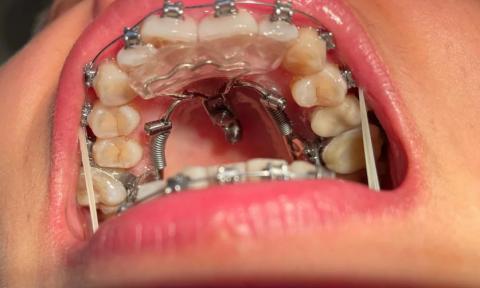

This image shows an upper jaw orthodontic setup consisting of fixed braces combined with a metal palatal expansion appliance. The appliance is anchored to the upper teeth and palate and is designed to widen the upper jaw while teeth are being aligned. Mild gum redness and plaque accumulation are visible, which are common during active orthodontic treatment.

Upper teeth fully visible with bonded orthodontic brackets

Palatal expander appliance attached to molars and palate

Lower teeth partially visible with braces

Metal palatal expander centered on the hard palate

Springs and screws applying transverse expansion force

Orthodontic brackets and archwire on upper teeth

Mild redness of gum tissue near brackets

Plaque retention areas around appliance components

Findings are consistent with active orthodontic palatal expansion

Appliance applies controlled force to widen the maxilla

Soft-tissue irritation likely related to appliance bulk and hygiene challenges

Orthodontic maxillary expansion phase

Appliance-related gingival and palatal irritation

Expander appears properly seated and symmetrical

Force elements intact

No visible breakage or displacement

Palatal tissue mildly inflamed

No visible ulceration or pus